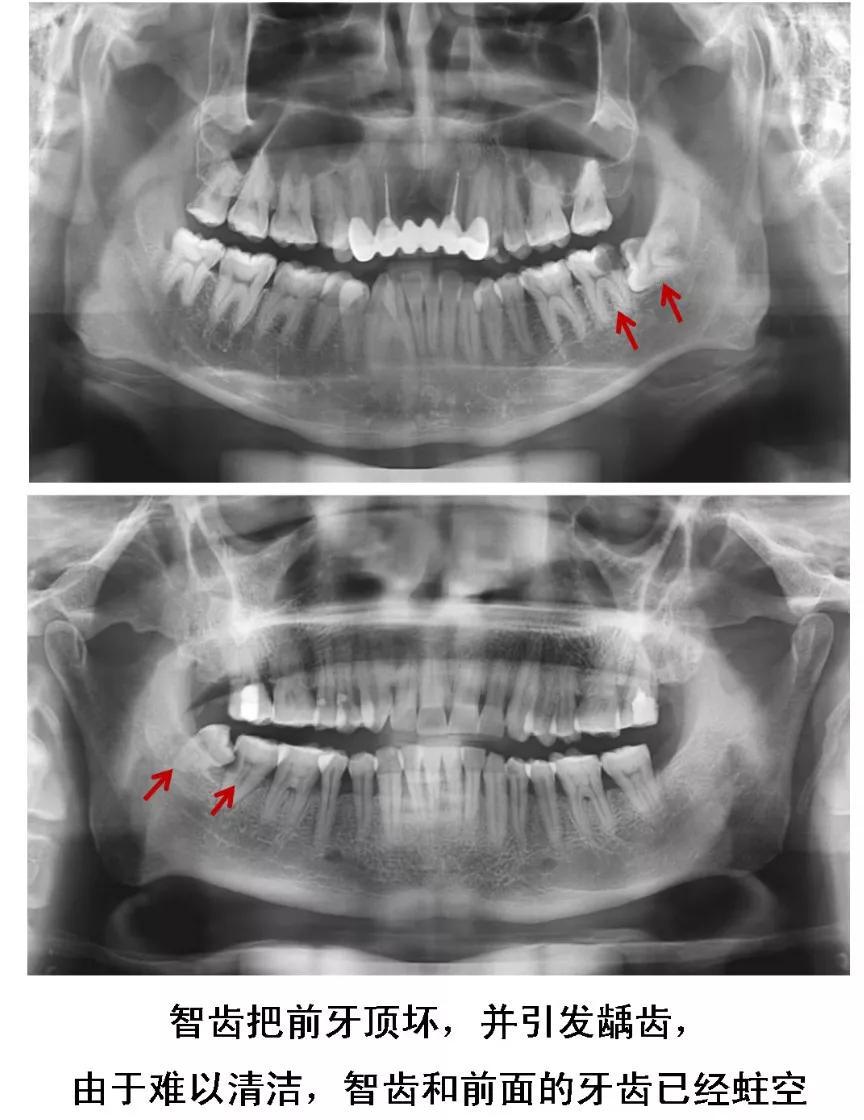

或是智齿生长的方向正好顶住邻牙,时间久了不仅会把邻牙顶坏,龋坏进一步发展会造成牙髓炎。